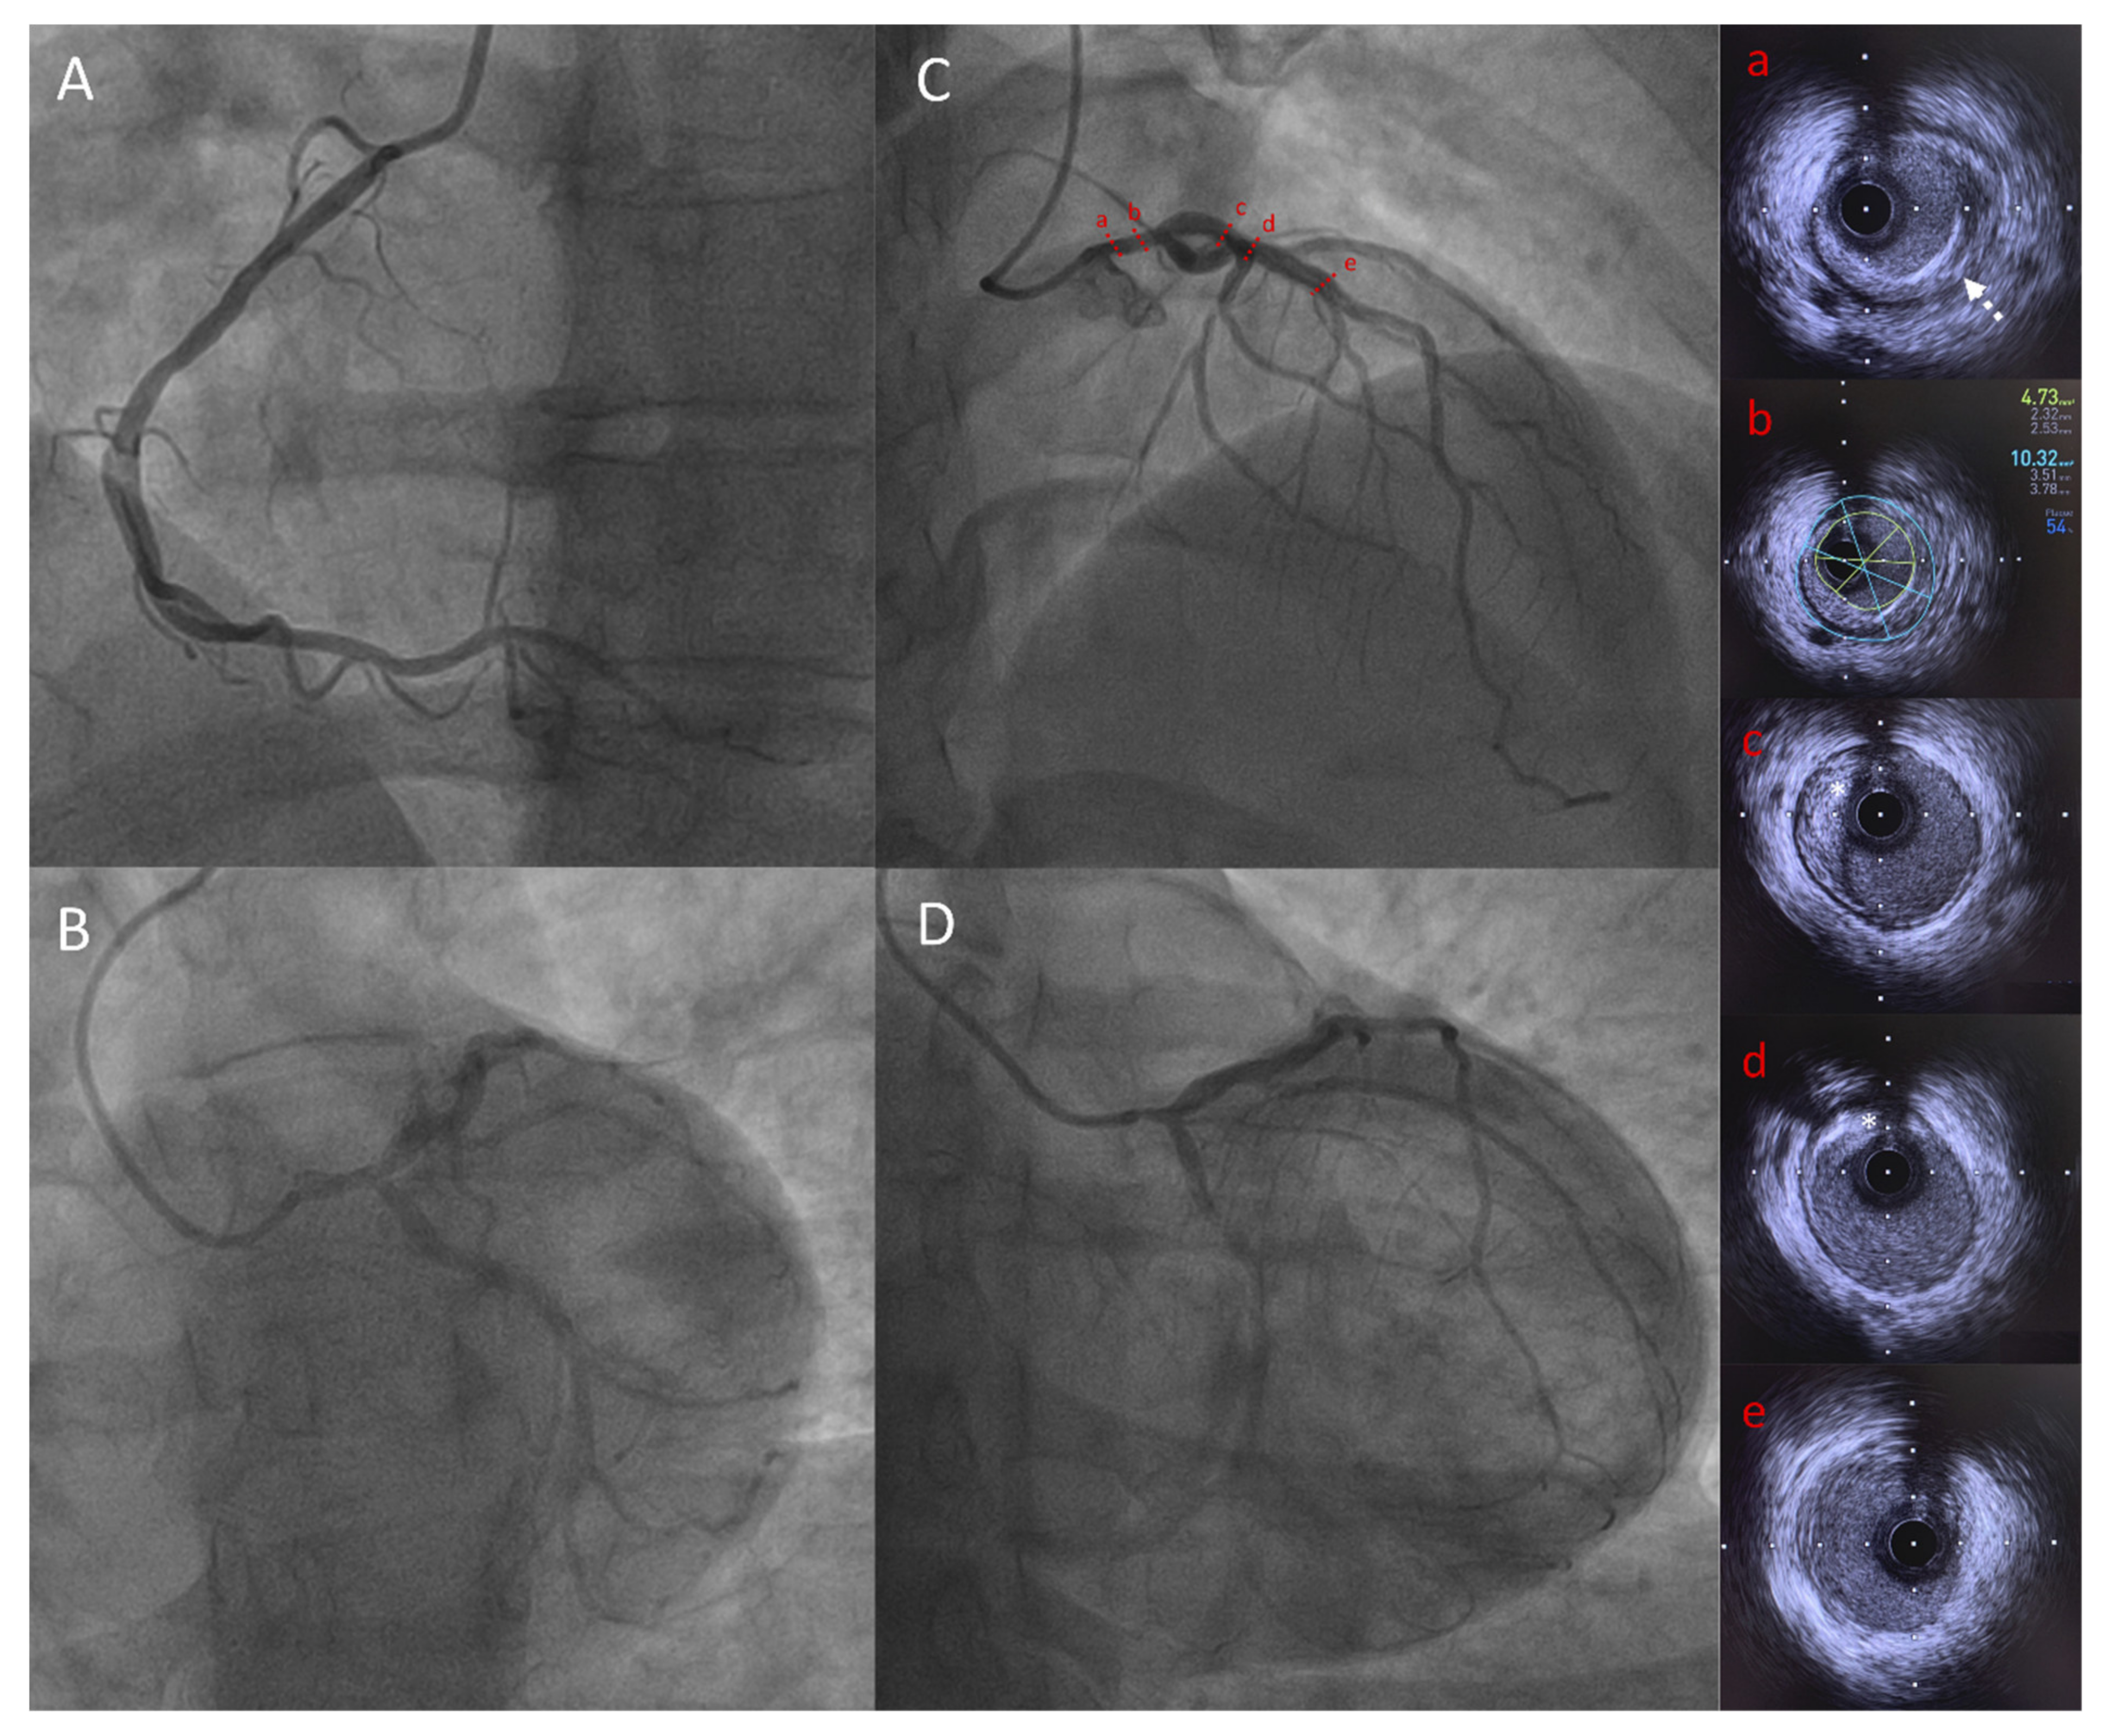

She was a non-smoker and her blood pressure was normal. Although she did not complain of any functional symptoms, cardiac investigations first aimed to detect a potential cardiomyopathy. The resting ECG was normal. The 24-h Holter monitoring showed atrial premature complexes without atrial fibrillation; PR, QRS and QT intervals were normal. The electrophysiological study did not show any conduction disturbance. The left ventricular ejection fraction was normal (LV ejection fraction: 65% assessed by echocardiography) and the cardiac MRI did not show any sign of dilated cardiomyopathy. A systematic ECG stress test was performed in this context of diabetes and lipodystrophy. The ECG stress test was stopped, as the patient developed breathlessness with a peak heart rate of 155 bpm (81% of the theorical maximum heart frequency), at 5.8 METs of work. In addition, down-sloping ST-segment depressions were observed in II, III, aVF and V3-V6 leads. The coronary angiogram revealed severe proximal and diffuse stenosis of the coronary artery territories, with ostial stenosis of both the right coronary artery (Figure 4A) and the left main coronary artery (LMCA) (Figure 4B–D). Intravascular ultrasound found a LMCA significant stenosis with circumferential calcifications (Figure 4a), and a severely decreased lumen area (4.73 mm2) (Figure 4b). The proximal left anterior descending artery was calcified (Figure 4c,d) whereas the mid part showed minimal atheroma (Figure 4e). The patient underwent a successful triple coronary artery bypass graft surgery.

Figure 4.

Coronary angiography and IVUS showing significant LMCA stenosis in Patient 2. Capital letters show coronary angiography: (A) Left anterior oblique view of right coronary artery; (B) Spider view of left coronary artery; (C) Right anterior oblique cranial view of left coronary artery showing tubular LMCA stenosis; (D) Right anterior oblique caudal view of left coronary artery showing tubular LMCA stenosis; Lowercase letters showing IVUS frames of LAD and LMCA: (a) LMCA stenosis with circumferential calcifications (white dotted arrow); (b) LMCA minimal lumen area measurement (4.73 mm2) demonstrating significant stenosis; (c) and (d) proximal LAD with calcified plaque (white star); (e) mid LAD showing minimal atheroma. IVUS = intravascular ultrasound, LMCA = left main coronary artery, LAD = left anterior descending artery.